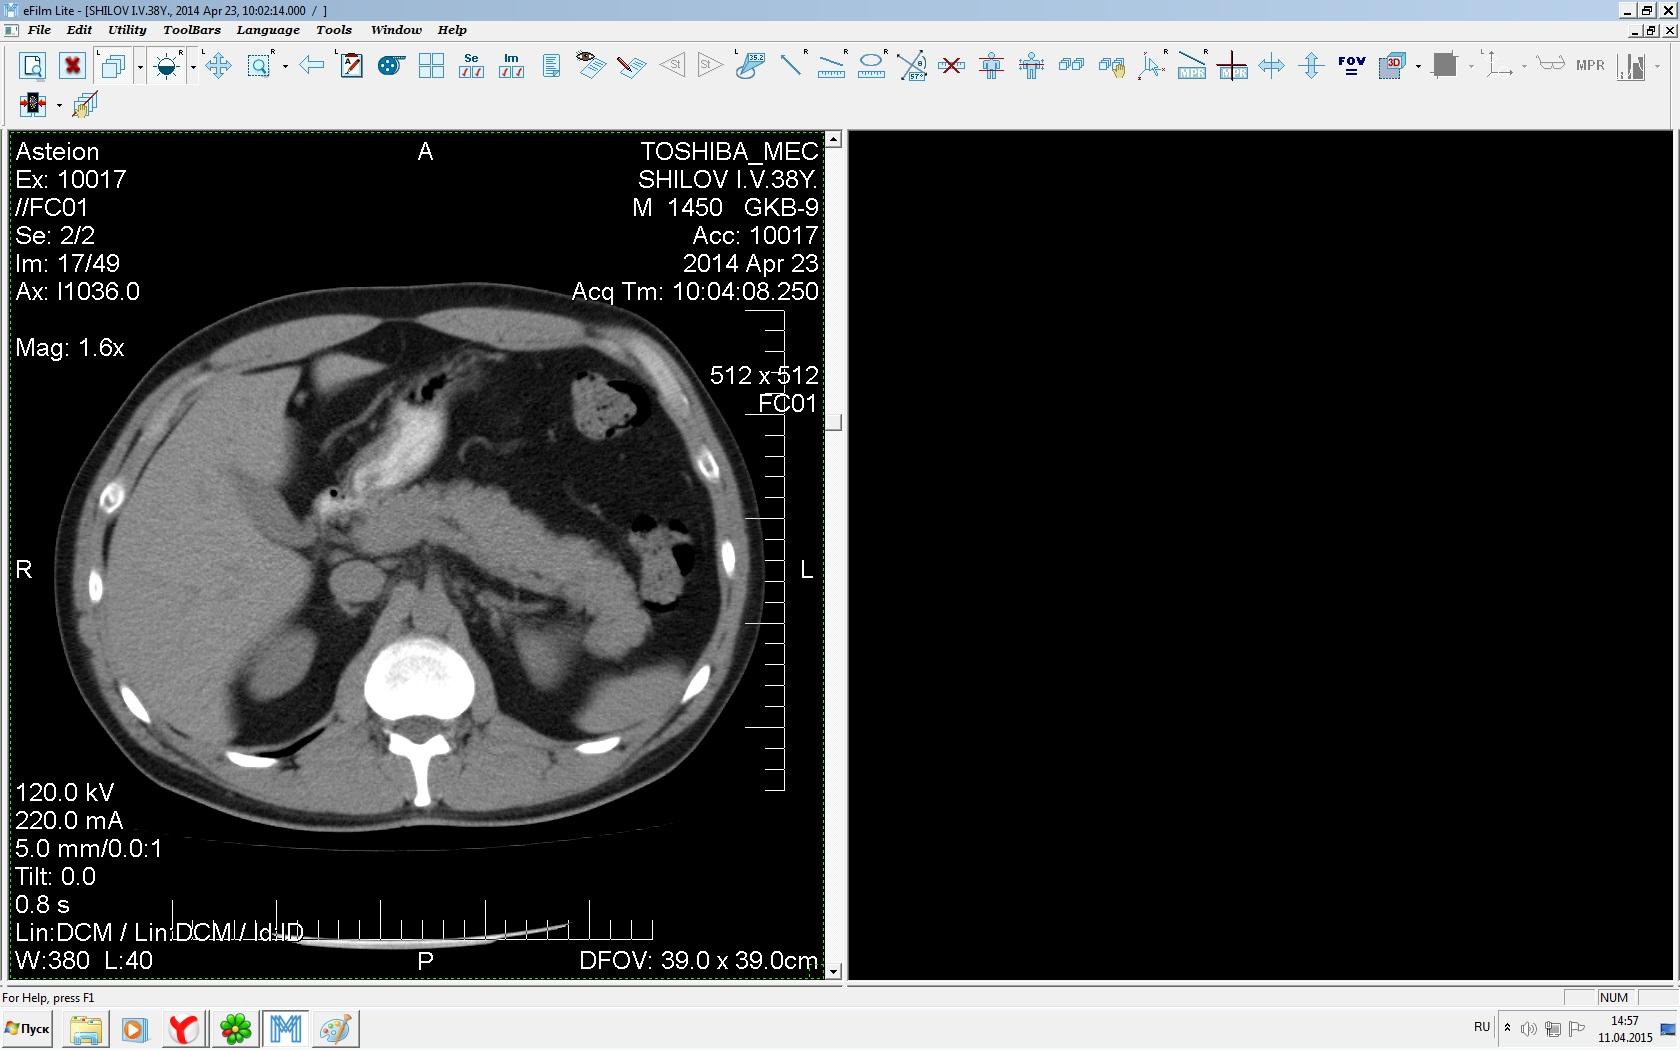

Здравствуйте. У меня киста левой почки. Из заключения: левая почка увеличена, деформирована за счёт наличия в среднем сегменте округлого жидкостного +6, +15 HU образования 66х53 мм, деформирует, поддавливает чаше-лоханочную систему. Сосудистые ножки структурные. В урологии мне сперва предложили лапароскопию, когда я лёг на операцию - изменили на полостную в связи со сложностью. Потом сказали что шансов вырезать кисту без почки практически нет. Даже если кисту удалить чудесным способом, то почка всё равно сложится и не будет работать. В итоге операцию отменили. Скажите, пожалуйста, есть ли современный метод удалить кисту и сохранить почку в моём случае? Томография почки в приложениях. Заранее благодарю.

Эту кисту можно просто пропунктировать, аспирировать и склерозировать - под местной анестезией. Ничего сверхестетственного не определяется по данным КТ. Можете написать мне на почту. aristova-tatyana@mail.ru